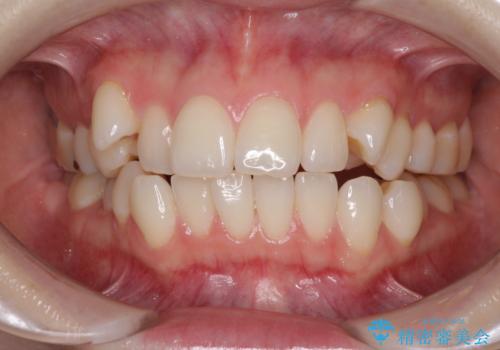

- 前歯のデコボコや八重歯の様になっていることを気にして来院された患者様です。

犬歯捻れて前方に飛び出しており、下顎前歯もそれに沿うようにデコボコとなっていました。

IPR(歯と歯の間を削る処置)によりスペースを獲得して上下顎前歯のデコボコを改善し、前歯が前方に突出しないように設定した上で、インビザラインにて矯正治療を行うこととしました。